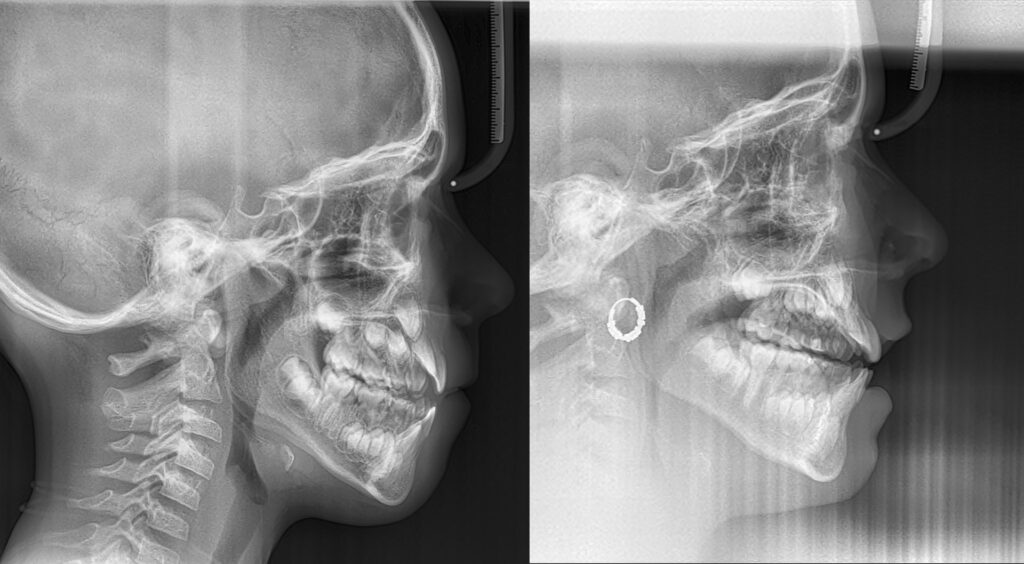

Paciente en tratamiento con un significativo crecimiento maxilar vertical.